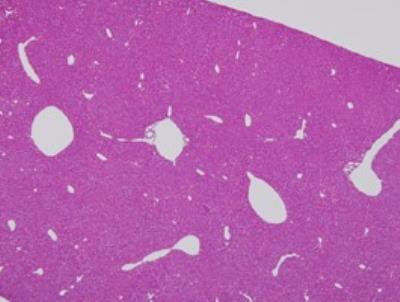

I think these maybe brain cells.

BRAIN CELLS:

All of these photos are not mine. the labels on the larger photo above these two are not mine either.

Brain cells found in my slides:

A lot of these look a little bit different but I think these are brain cells.

These a look a little bit different than the ones above, so I am not 100% sure that they are the same type of cells.